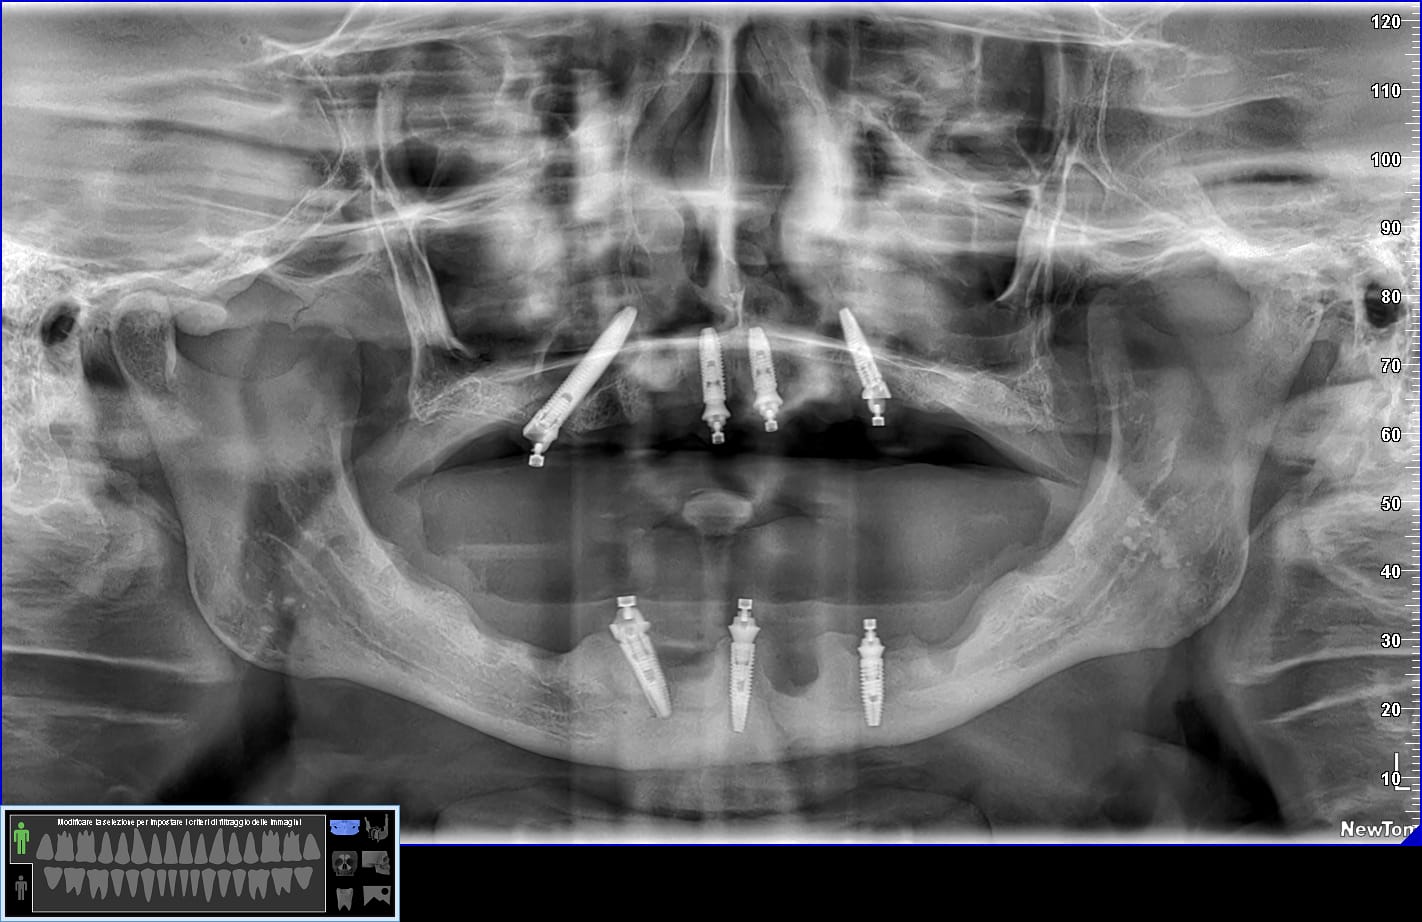

Effettivamente ci sono impianti vecchi da rimuovere e l’osso è scarso.

Nel caso di oggi vedremo il posizionamento di un impianto transinusale in questo paziente:

Durante la chirurgia dovrò gestire una perforazione rilevante della membrana del seno.

Ah… questa è la panoramica finale, inferiormente non ho trovato il modo per mettere 4 impianti ma solo tre… vedremo se aggiungerne uno. E non farti ingannare dall’immagine: il mentoniero di destra non è quello che sembra più distale ma quello meno visibile più mesiale.